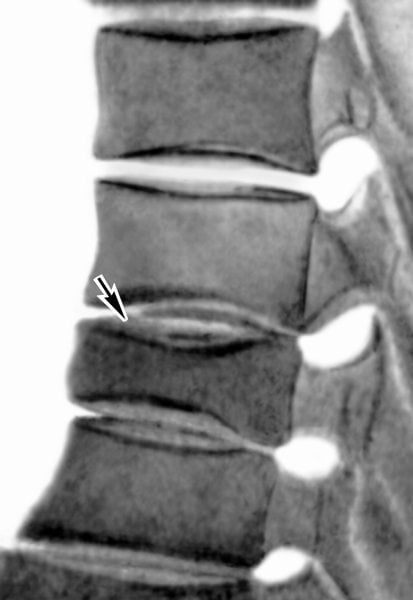

А в это время медленно, неуклонно разрушаются диски, деформируются тела позвонков с образованием острых костных шипов — остеофитов. Они сдавливают мягкие ткани, ущемляют спинномозговые корешки, что и приводит к появлению болей.

- МРТ или КТ позвоночника;

- рентгенографии в 2 и более проекциях;